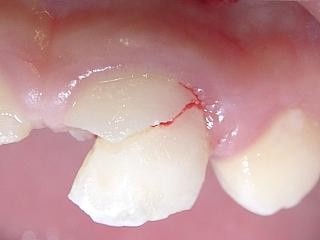

複雑性歯冠破折:露髄を伴い、エナメル質、象牙質、セメント質に及ぶ破折 (図2、3)

複雑性歯冠破折の場合(図2,3)

強い冷温水痛、あるいは、強い自発痛があります。

歯髄保護をしたのち、レジン樹脂などで破折部の修復を行います。

しかし歯髄への傷害が大きい場合には歯髄除去(抜髄)が必要に成ります。